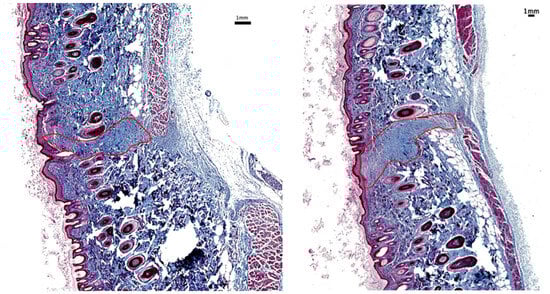

Figure 8 and Figure 9 are representative images of wound histology at 16 days and 2 months post-surgery, respectively. The difference in the amount of scar produced by the EB versus the SB is apparent. In addition, the scar area width is narrower along the incision made with the EB in comparison with that corresponding to the SB.

Figure 8.

Scar histology 16 days post-surgery: Histological sample stained with trichrome at 16 days post-surgery showing less scarring in region of EB skin incision (left) than SB skin incision (right).

Figure 9.

Scar histology 2 months post-surgery: Histological sample stained with trichrome at 2 months post-surgery showing less scarring in region of EB skin incision (left) than SB skin incision (right).

Figure 7 presents the average values of the C = ratio measuring the decrease in the granulation tissue deposition area in the skin incisions made with the experimental blade CEB relative to the area of skin incisions made with standard blades CSB. The amount of granulation tissue was reduced more in the wounds made with nanometric-scale-polished surgical blades. We observed that C at all time points, which means that notably less granulation tissue occurred in skin incisions made by EBs in comparison with SBs. Generally, the reduction in the granulation tissue deposition area in skin incisions made with the EB ranged between 30% and 50% during the proliferation phase and reached approximately 90% 6 months post-incision, with the magnitude of the standard error of the mean being approximately 25% of the mean on day 7 and about 45% of the mean on day 16 and 6 months post-operation.